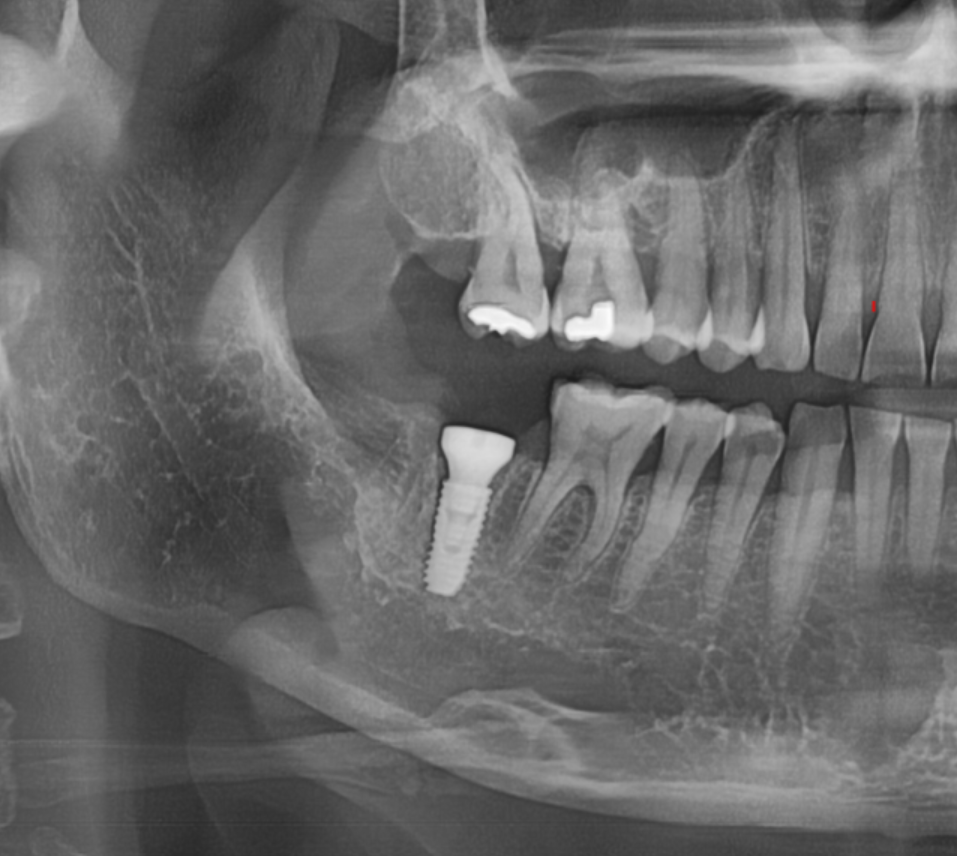

치아 내부가 충치가 심하거나

내부에서 깨져버리면 크라운을 다시 붙일 수 있는 지지대가 없어져

치료가 어려워집니다.

충치가 신경과 뿌리까지 내려가 치아 구조가 무너진 경우

치아가 뿌리에서 파절된 경우

크라운을 지탱할 남은 치질이 거의 없는 경우

250724 남아있는 치질이 거의 없는 경우

250327 내부 충치가 너무 심하면 발치 후 임플란트가 필요합니다.